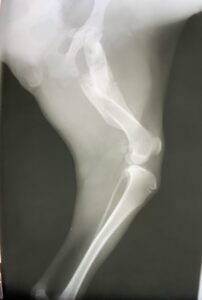

Maisey Fracture